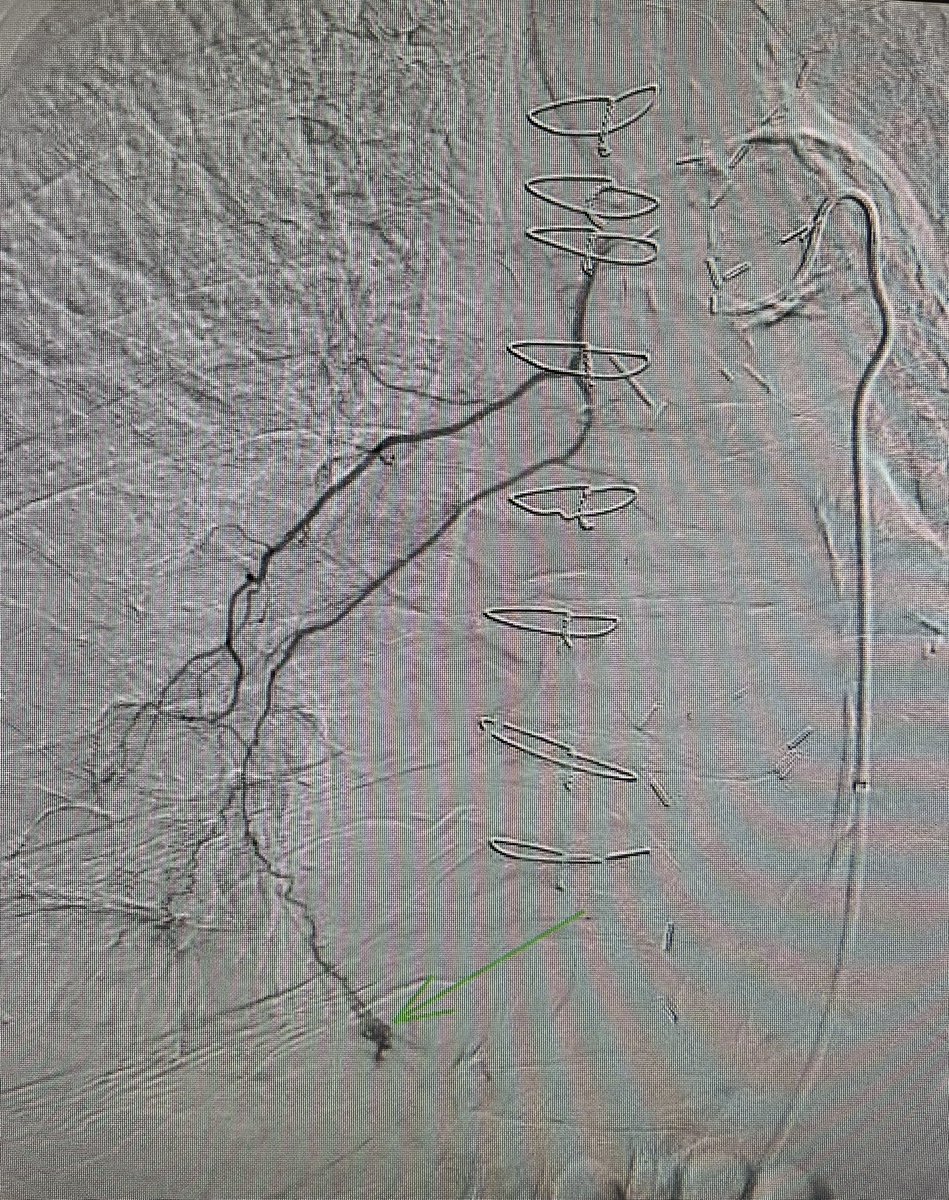

One of the 1st studies in healthcare using @HoloLens 2, supported by @RSNA. #AugmentedReality guidance improves procedure times and radiation dose. Med students also instantly elevated to #IRAD attending level! @dotter_IR @Penn_IR @PigiLab @SIRRFS rdcu.be/b9p98